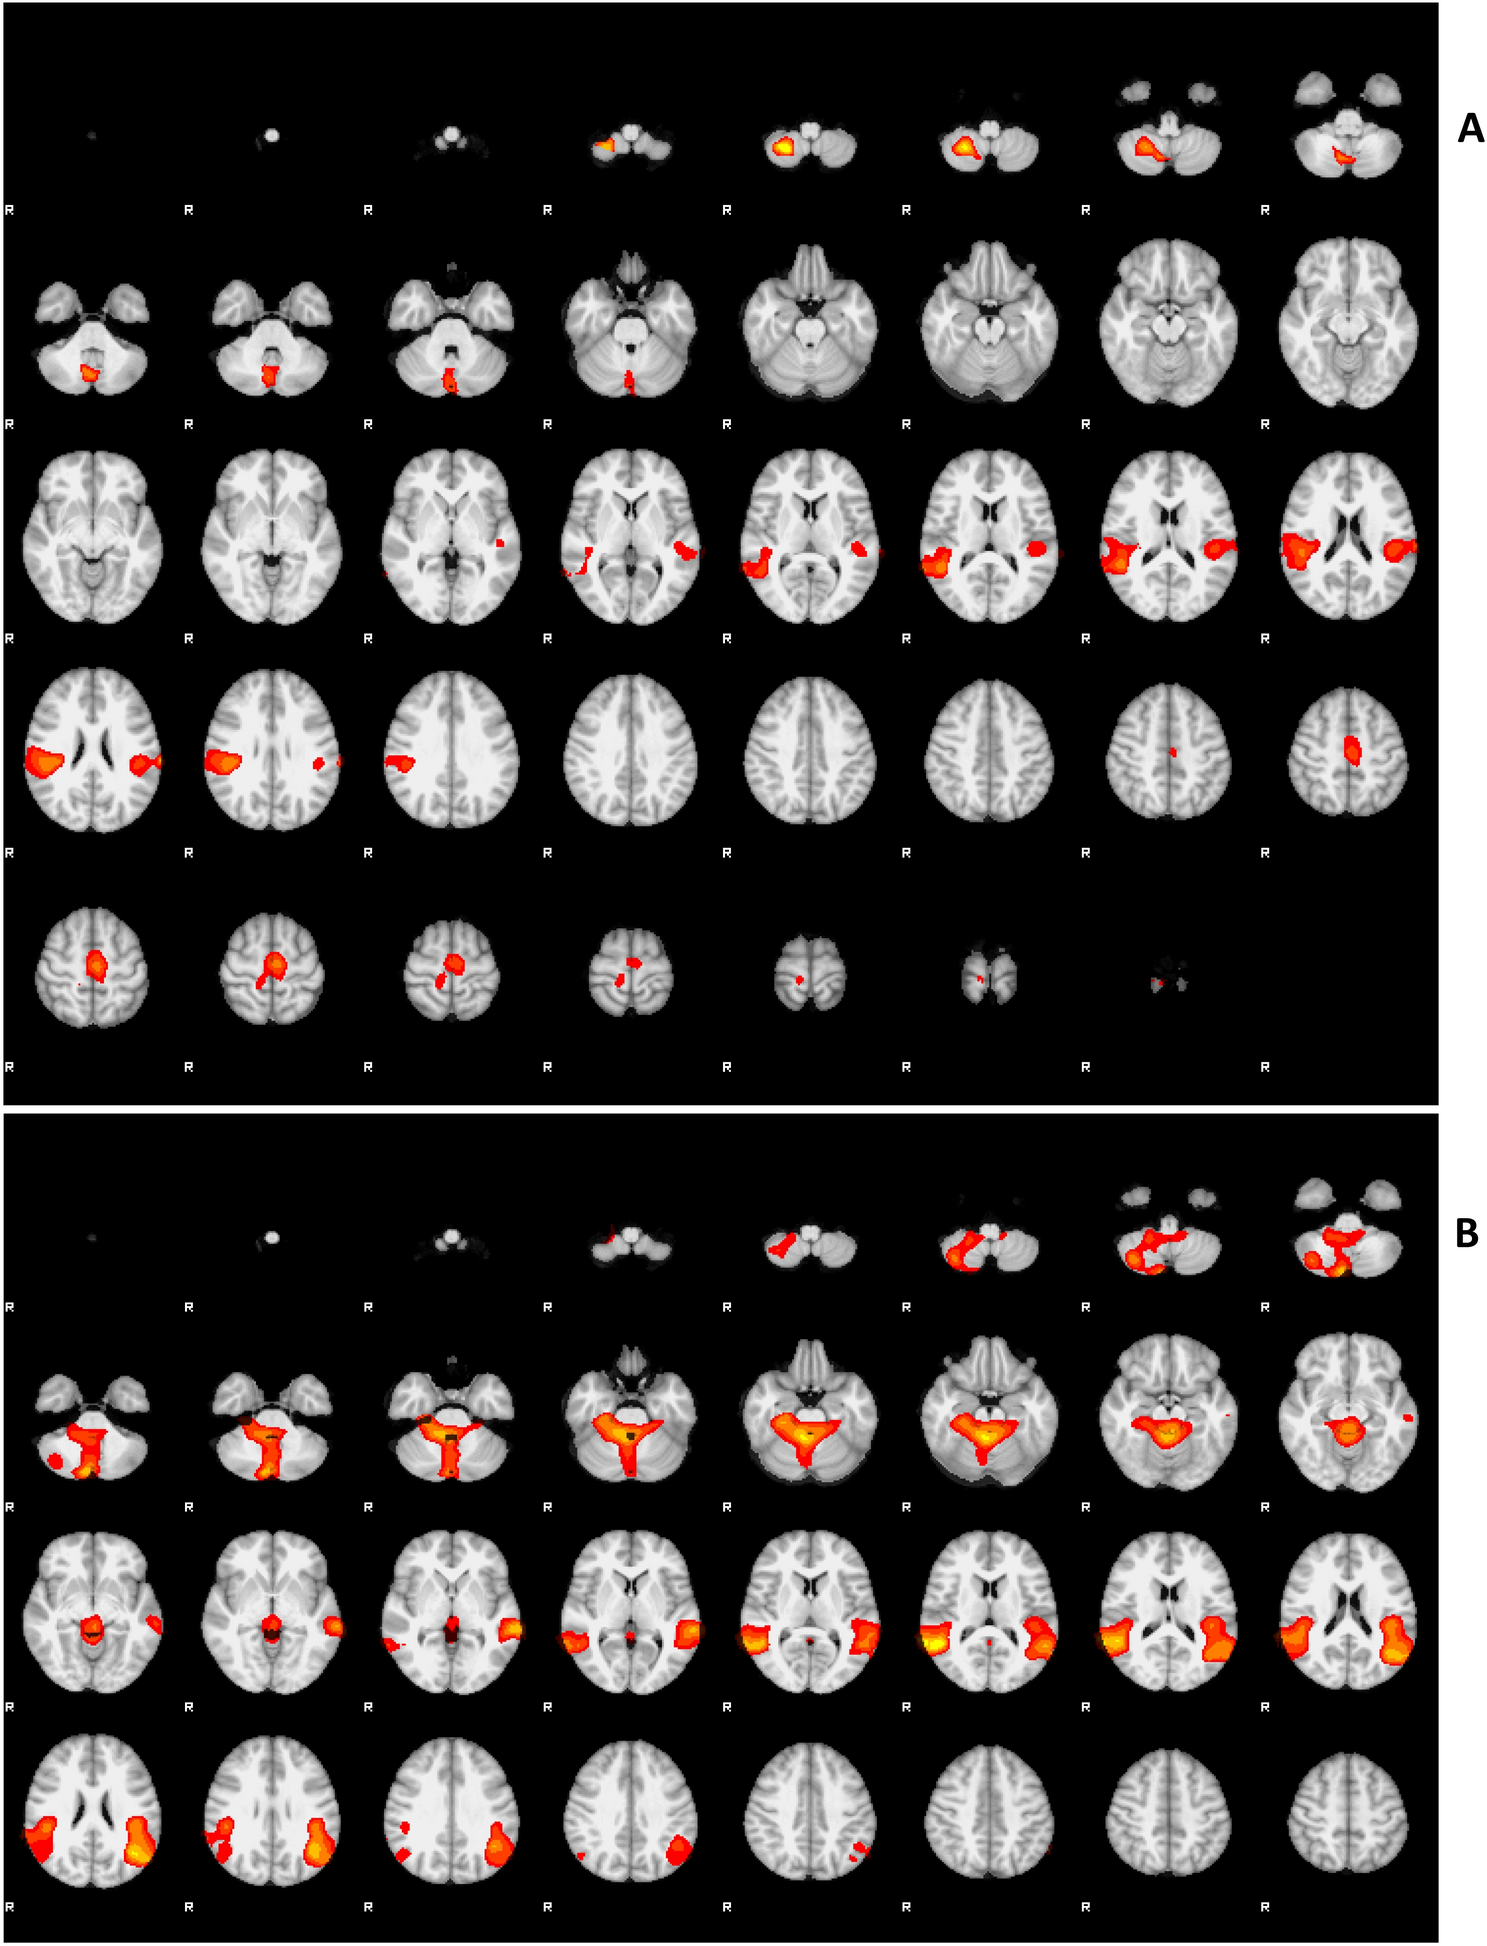

Figure 4

From: Respiratory function modulated during execution, observation, and imagination of walking via SII

GLM analysis showing the effect of the RR time course during Execution condition (A) and all three conditions (Execution, Imagination, and Observation) (B) in the group. The activity displayed in this parametric map was explained by the time course of RR parameters not using estimation parameters of the tasks performed by the subjects. Clusters determined by Z > 3.1, cluster significance threshold of P < 0.05 corrected38.